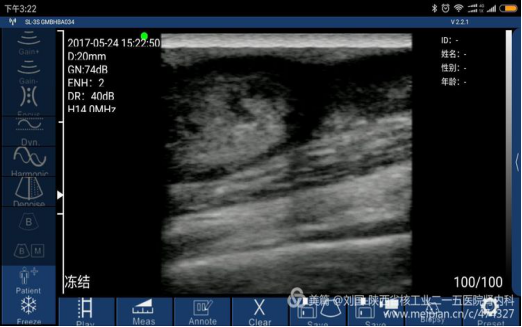

索诺星无线超声所查的结果,显示器是我的小米max。

索诺星无线超声检查的头静脉情况,显示器是我的小米max。